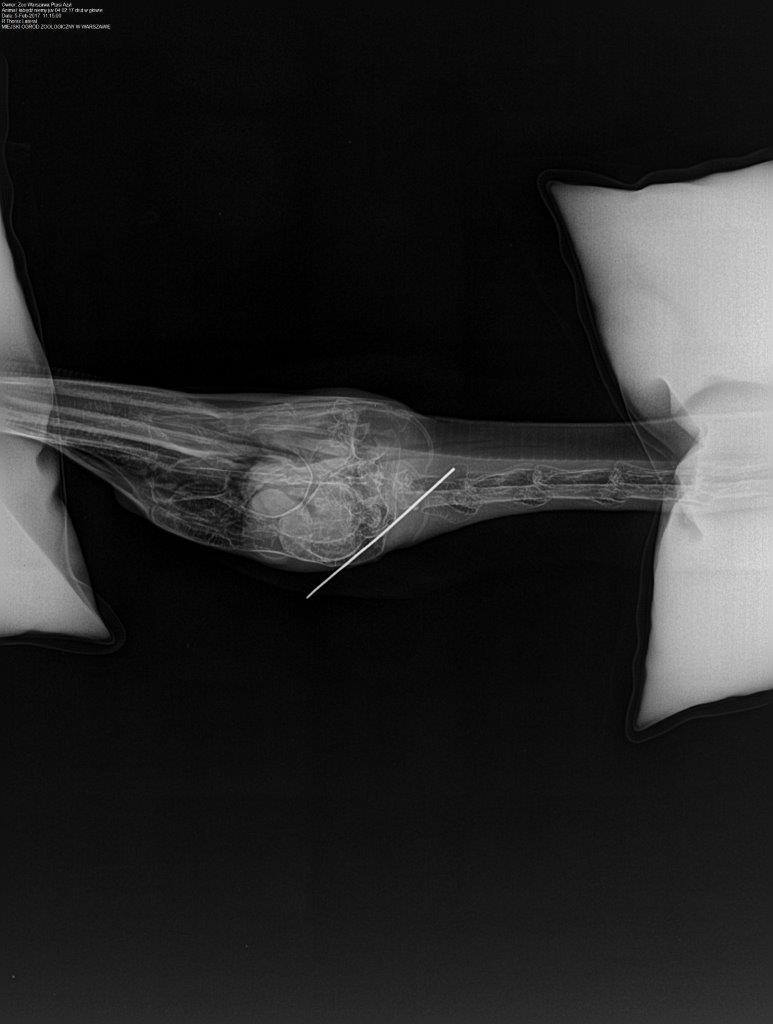

- Fot Facebook/Ptasi Azyl

Dzisiaj w narkozie wykonaliśmy zdjęcia RTG głowy, które na szczęście wykazały to co podejrzewaliśmy – metal utknął w czaszce ale w przestrzeni gdzie znajdują się zatoki, a więc ominął mózg. Kilka minut później usunęliśmy drut a łabędź wybudził się bez większych problemów. Nietypowy pacjent po kilku godzinach dołączył do innych łabędzi.